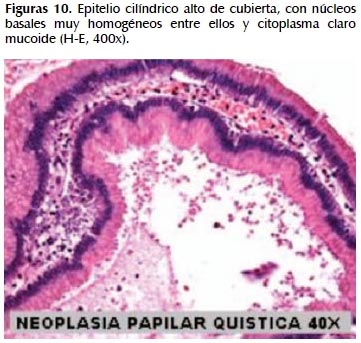

La alteración fundamental en este caso es la presencia de marcada dilatación de los conductos pancreáticos (Figuras 6, 7, 8, 9, 10 y 11) con variable hiperplasia de los conductos menores periféricos.

Los quistes están limitados por células ductales altas, algunas mucinosas, en su mayor extensión dispuestas en una fila. De manera focal se ve proyecciones papilares del epitelio y también focos de erosión con reacción inflamatoria, exudado linfocitario y formación de tejido de granulación.

El resto del parénquima pancreático muestra múltiples focos de autolisis y variable hiperplasia de los ductos.